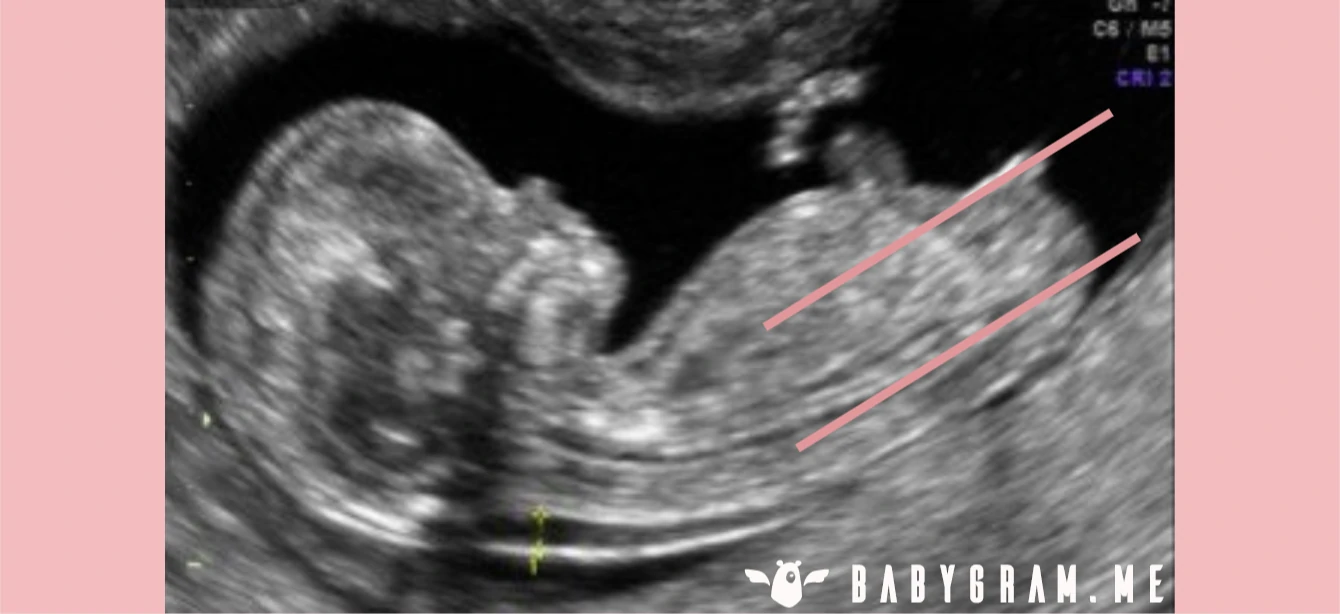

Our experts use the well-known nub theory to help identify the gender of your unborn child based on your first trimester ultrasound. The nub is your child's indeterminate sexual organ, which will transform into a penis or a clitoris during the second trimester of pregnancy. In practice, the nub theory consists of analyzing the angle between your child's nub and its spine during the ultrasound. You can see a girl and a boy example on the images below and read more explanations in our detailed article.

BABYGRAM uses the genital bud method to analyze your ultrasound when the conditions for this method to be accurate are met. This method has an average reliability greater than 90% for ultrasounds performed after 12 weeks of pregnancy (14 weeks after your period) and for fetuses whose cranio-caudal length is greater than 60mm, when the ultrasound image reveals the entire nub.